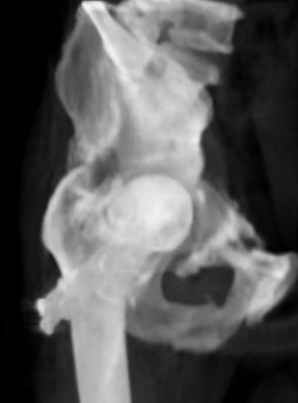

Уважаемые коллеги, Мужчина 1952 г.р. поступил в 36 больницу Екатеринбурга 1 июня 2004 г. Диагноз: Множественный перелом ребер слева, субтотальный гемоторакс, оскольчатый перелом шейки правого бедра. Повреждение таза не диагностировано.

17 июня 2004 г. - открытый остеосинтеза шейки бедра винтами с костной аутопластикой. Заживление раны первичное. Выписан 1 июля. 4 июля отметил укорочение конечности. При контрольном осмотре через 1 месяц после остеосинтеза - передний вывих бедра. Неправильно срастающийся перелом костей таза. Вопрос - особенности эндопртезирования тазобедренного сустава в этой ситуации?